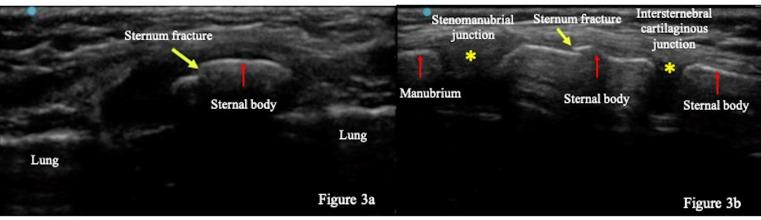

A previously healthy, 4-year-old boy visited our emergency department due to chest pain after a fall from a skate scooter. Physical examination revealed tenderness over the sternal body. Point of care ultrasound (POCUS) of the sternum demonstrated a discontinuation of a hyperechoic structure of the sternal cortex, suggesting a sternal fracture. POCUS did not detect intraperitoneal fluid, pericardiac effusion, or pneumothorax. Plain radiograph confirmed the diagnosis of isolated sternal fracture and the patient was discharged with conservative treatment. POCUS was useful not only in diagnosing a sternal fracture but also to rule out concurrent injuries.